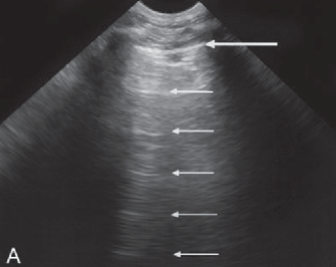

Strong ___ ___ from other nearby ___ devices can create ___ patterns

In the image, we see horizontal lines traveling through the image, especially at the bottom (far field)